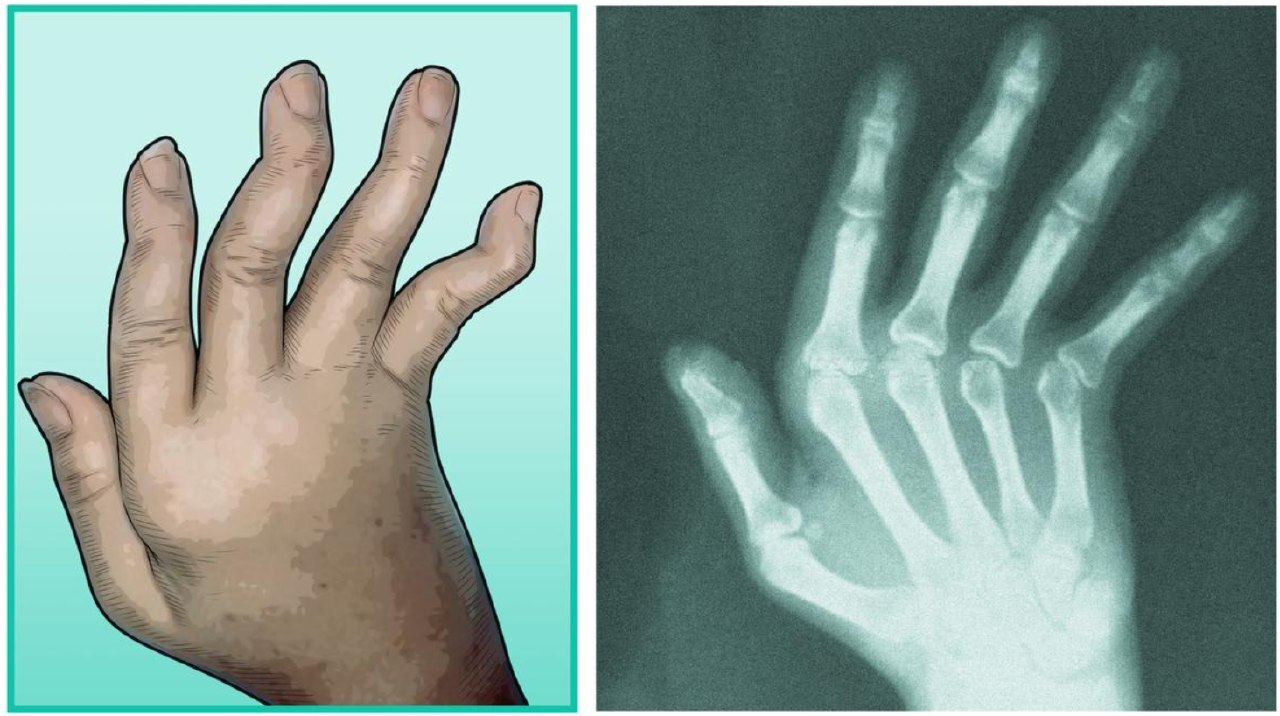

🔹 Essa artrite dá febre reumática não costuma dar sequelas. PORÉM RARAMENTE PODE CAUSAR A ARTROPATIA DE JACCOUD. JA CAIU NO REVALIDA. LEMBRAR QUE É UMA FROUXIDÃO LIGAMENTAR QUE CAUSA UM DESVIO DAS ARTICULAÇÕES DAS MÃOS, MAS ESSE DESVIO NÃO TEM RELAÇÃO COM ALTERAÇÃO ÓSSEA E COM A SIMPLES MOVIMENTAÇÃO A ARTICULAÇÃO VOLTA AO NORMAL. OU SEJA, UMA SEQUELA REVERSÍVEL.

A artropatia de JACCOUD é caracterizada pela frouxidão ligamentar e da cápsula articular gerando deformidade do tipo reversível, já que não gera erosão óssea como na artrite reumatoide. A artropatia de JACCOUD está muito associada a que doença?

Lúpus eritematoso sistêmico (LES) e febre reumática.